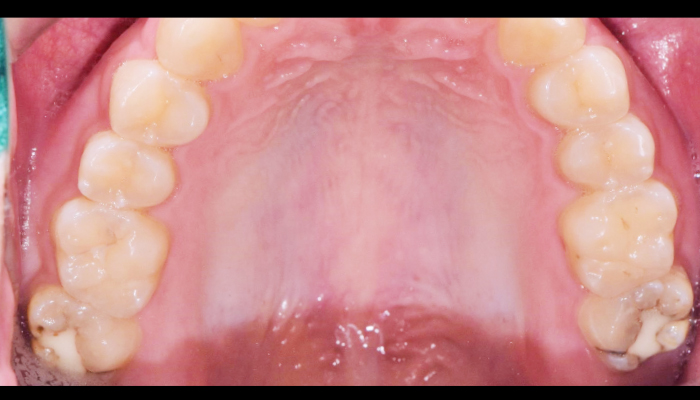

스케일링은 칫솔질로 제거되지 않은 치석과 치태를 제거하여 치석으로 인한 잇몸질환, 충치, 구취 등을 예방하는 치료입니다. 최근에 건강보험이 적용되어 1년에 한 번, 보험 혜택을 통해 스케일링을 받으실 수 있습니다.

스케일링 이런분께 추천드립니다!

다음과 같은 경우 스케일링 치료를 통해 건강한 치아로 회복하실 수 있습니다.